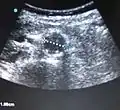

يشخص تمدد الشريان الأبهري البطني عادة بواسطة فحص بدني، أو بمسح الموجات فوق الصوتية، أو بالتصوير المقطعي. قد تظهر صور أشعة البطن الخطوط العريضة لتمدد الأوعية الدموية عندما تكون جدرانه متكلسة. وهذا هو الحال في أقل من نصف حالات تمدد الأوعية الدموية. يستخدم التصوير بالموجات فوق الصوتية للكشف عن تمدد الأوعية الدموية وتحديد حجم أي من الموجود. بالإضافة إلى ذلك، يمكن الكشف عن السائل البريتوني وهى من الوسائل الغير تداخلية وذات حساسية عالية، ولكن وجود الغازات في الأمعاء أو وجود السمنة قد يحد من فائدتها. الاشعة المقطعية ذو حساسية لاكتشاف تمدد الأوعية الدموية ما يقرب من 100 ٪ ومفيد أيضا في التخطيط السابق للجراحة، تفاصيل التشريح وتركيب جسم المريض وإمكانية إصلاح الأوعية الدموية من الداخل. في حالة تمزق التمددالمشتبه به، فإن يمكنه أيضا الكشف عن السوائل خلف البريتون. بدائل قليلا ما تستخدم كأساليب التصوير لتمدد الأوعية الدموية وتشمل التصوير بالرنين المغناطيسي وتصوير الأوعية.

الموجات فوق الصوتية لشريان أورطي بطني طبيعي قياس 1.9 سم في القطر.